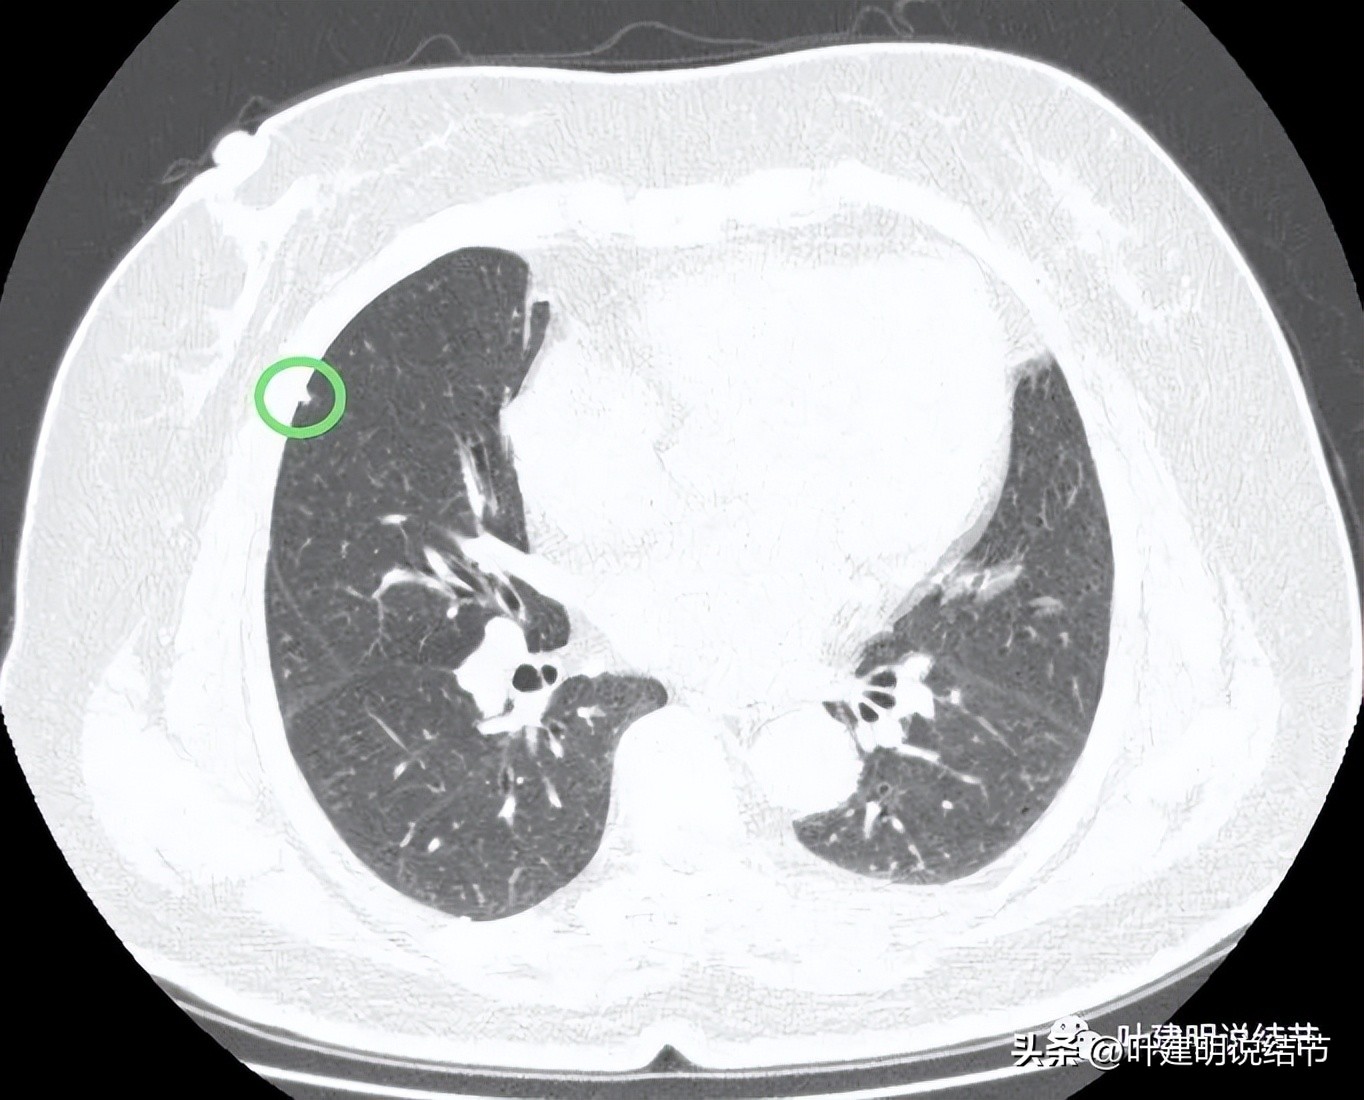

病灶1:右上叶实性小结节,密度高,胸膜下,考虑良性可能性大